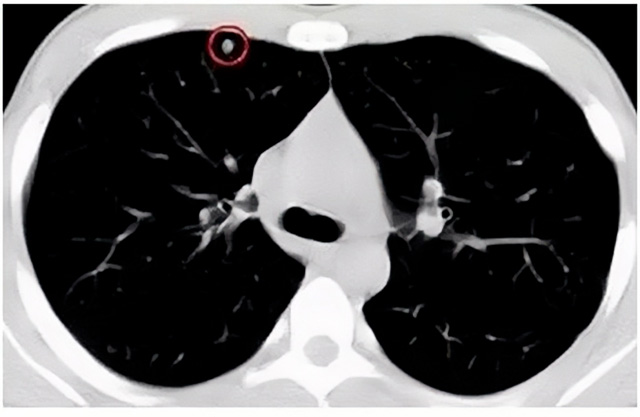

移動(dòng)CT體檢車可以檢查肺結(jié)節(jié)發(fā)現(xiàn)早期肺癌

移動(dòng)CT體檢車可以做肺部檢查。隨著多層螺旋CT肺部低劑量掃描的臨床應(yīng)用,目前很多人選擇肺部CT作為常規(guī)檢查項(xiàng)目,較大地提高了肺結(jié)節(jié)的檢出率。如果檢查發(fā)現(xiàn)肺部有肺結(jié)節(jié)是磨玻璃型的,小于5mm的微小結(jié)節(jié),大部分都是良性的。如果達(dá)到1CM以上的,很有可能有肺癌的機(jī)率。根據(jù)其內(nèi)密度不同可分為磨玻璃結(jié)節(jié)、實(shí)性結(jié)節(jié)、部分實(shí)性結(jié)節(jié)。根據(jù)其大小可分為肺大結(jié)節(jié)、小結(jié)節(jié)和微小結(jié)節(jié)。如果是炎癥性肺結(jié)節(jié),幾個(gè)月后復(fù)查有變化變小就不用做手術(shù)。如果CT再次復(fù)查結(jié)節(jié)沒有變化,沒有縮小就需要升級(jí)做病例檢查。病理檢查的確診性是最高的。是有沒患癌的標(biāo)準(zhǔn)。檢查發(fā)現(xiàn)早的話,規(guī)范手術(shù)治療,手術(shù)后5年的存活率很高的。肺癌這個(gè)要早發(fā)現(xiàn)早治療。

現(xiàn)在的移動(dòng)CT體檢車的分辨率比X光高,CT掃描的圖像越來越薄顯像更清晰,檢查更準(zhǔn)確。得到了普及,肺結(jié)節(jié)的測(cè)出率很高的。但是顯浩告訴大家,肺結(jié)節(jié)不等于肺癌。雖然很多是良性,但是很多肺癌都是肺結(jié)節(jié)發(fā)展來的。 必須定期檢查復(fù)查。磨玻璃結(jié)節(jié),肺癌的機(jī)率較高。肺癌是惡性腫瘤病死率最高的。除了環(huán)境,遺傳,等因素。吸煙,從事煙霧工作行業(yè)的人員比較危險(xiǎn)。發(fā)病比例高。肺部疾病早發(fā)現(xiàn)早治療,依舊是肺部疾病的治療標(biāo)準(zhǔn)。

一旦CT檢查發(fā)現(xiàn)肺結(jié)節(jié),若不規(guī)律復(fù)查,檢查等同于白檢。所以在復(fù)查中,如果結(jié)節(jié)中發(fā)現(xiàn)有增大的趨勢(shì),或大小發(fā)生了變化,我們必須提請(qǐng)注意及時(shí)治療,不要掉以輕心。移動(dòng)CT體檢車的普及化,讓肺部檢查更準(zhǔn)確更高效。發(fā)現(xiàn)肺結(jié)節(jié)時(shí),及時(shí)就醫(yī)并進(jìn)行專業(yè)評(píng)估是確保準(zhǔn)確分類和采取適當(dāng)措施的關(guān)鍵。